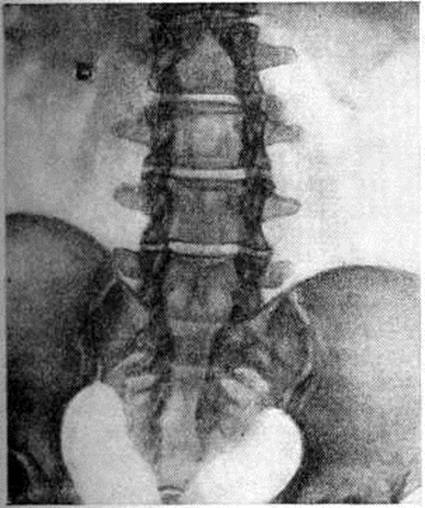

Рис. 6.

Рентгенограмма пояснично-крестцового отдела позвоночника при резко выраженной spina bifida: просветление на уровне тел поясничных позвонков и в средней части крестца обусловлено отсутствием задних отделов дуг, остистых отростков и задней стенки крестцового канала.

При выраженных нарушениях развития дуг позвонков на рентгенограммах обнаруживают их обширные дефекты с отсутствием изображения остистых отростков, задних отделов, а иногда и суставных отростков и даже ножек дуг (рисунок 6). Обнаружение Спина бифида должно побудить к поиску других проявлений спондилодисплазии (локальных сужений позвоночного канала, межпозвоночных отверстий, вариантов расположения суставных отростков, деформации тел позвонков, чаще клиновидной, и другие).